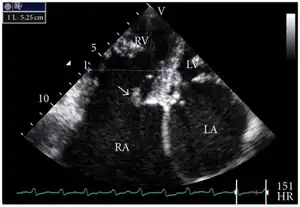

Transthoracic echo: TR (arrow)